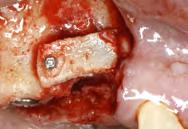

Figura 3. Lesión macroscópica

Bajo anestesia general, se realizó la escisión quirúrgica de la lesión, junto con la extracción del canino superior izquierdo de la primera dentición impactado. El tumor era de color marrón y medía aproximadamente 50 × 13 mm.

La muestra se envió para análisis histopatológico (Figura 3).